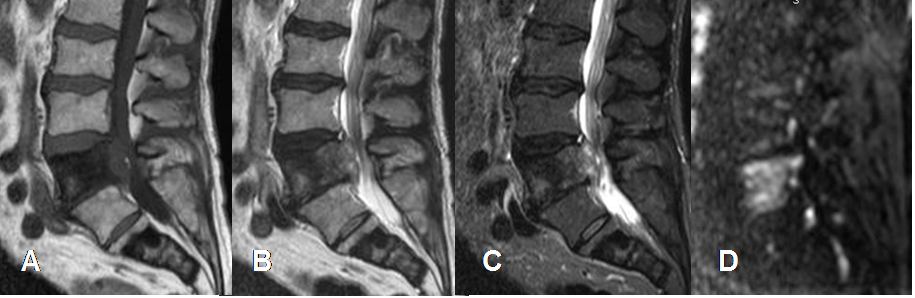

Fig 30. Metástasis blástica.

A: RM sagital en T1, B: RM sagital en T2. C: RM sagital en STIR y D: RM sagital en difusión. Lesiones que comprometen L5 y S2 hipointensas en T1 y T2, algo hiperintensas en STIR e hiperintensas en la difusión, por metástasis blásticas secundarias a tumor de mama.